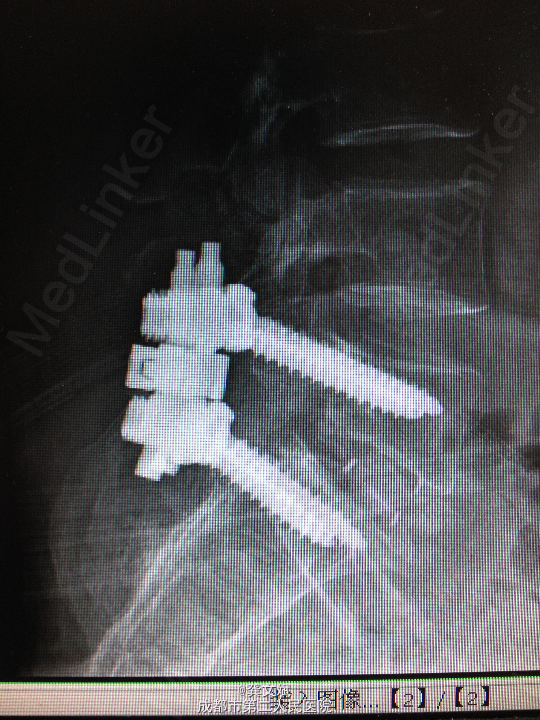

诊断:腰5椎体滑脱(I°)、腰5椎体双侧峡部裂 处理:腰5椎间盘摘除、滑脱复位、椎间植骨融合内固定

经过一段时间的愈合,得到很好的效果。